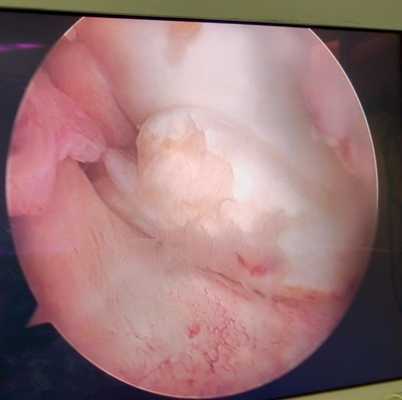

Разрыв внутреннего мениска по типу «ручки лейки» с блоком коленного сустава (невозможность полностью разогнуть коленный сустав). На фотографии хорошо виден крупный фрагмент мениска плотно зажатый между суставными поверхностями бедренной и большеберцовой кости.

Удалённый фрагмент внутреннего мениска при разрыве по типу ручки лейки с блоком коленного сустава.

Мениск после обработки по поводу паракапсулярного субтотального разрыва по типу ручки лейки.